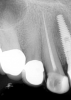

A patient had been seen for caries control and replacement of deteriorating amalgam restorations. Two weeks postoperatively, the patient was unable to tolerate hot or cold temperatures and was unable to chew any type of food (Figure 5). The patient accepted endodontic therapy, post and core, and full-crown coverage at a later date. The principles of the rotary-file system were used again.

Fig 5. Preoperative No. 14 maxillary left first molar.

Figure 5